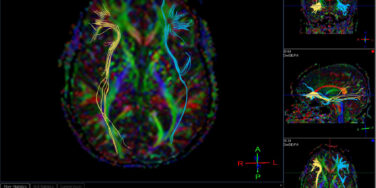

Inside the Dyslexic Brain: